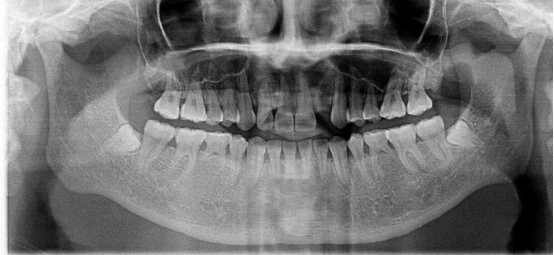

郭先生今年67歲,是位白手起家的成功企業(yè)家。早期忙碌的工作讓他疏于口腔保健,導(dǎo)致他上下牙列缺失。郭先生表示在二十年前在國(guó)外已經(jīng)做過種植牙,但是近期來我院就診時(shí)其之前種植牙的種植體已經(jīng)滑入到上頜竇內(nèi)。

“患者前牙骨量不足,壁薄,后牙因手術(shù)取出以前的種植體導(dǎo)致了骨頭的大量缺損,所以需要植骨才能進(jìn)行種植牙手術(shù)。種植需要避開手術(shù)后的骨缺失區(qū),所以對(duì)種植體的承受力和穩(wěn)定性要求較高,同時(shí)患者對(duì)美觀要求較高。”劉斌元教授在了解了患者的需求與口腔情況后為他進(jìn)行了植骨手術(shù),傷口愈合后,劉斌元教授為他進(jìn)行CT掃描后確認(rèn)可以進(jìn)行種植牙手術(shù)。